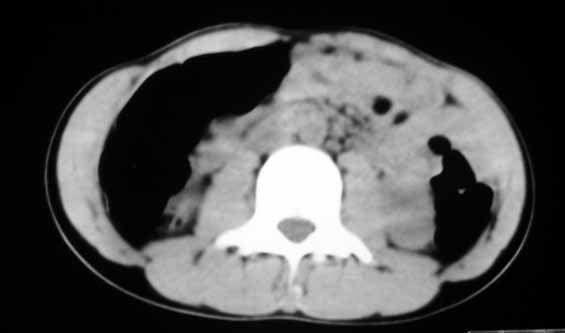

以下是引用余辉在2007-5-22 20:42:00的发言:[br]黄疸,脾脏巨大,病程短,考虑急性肝脏疾病或急性溶血性疾病,建议查肝功能及相应病毒抗体抗原

以下是引用zhangzhongshou在2007-5-22 21:04:00的发言:[br]1、脾肿大[br]2、脾脏低密度影,血管瘤?脾梗塞不能除外,建议增强扫描。

以下是引用dyqct在2007-5-22 20:45:00的发言:[br]巨脾,可疑梗塞,建议增强、查血象进一步检查

以下是引用liuyue在2007-5-23 7:57:00的发言:[br]腹主动脉周多个肿大淋巴结,脾大伴三角形低密度影,肠腔积气,考虑:1淋巴瘤2脾大伴梗塞3肠腔积气(肿大淋巴结压迫所致)